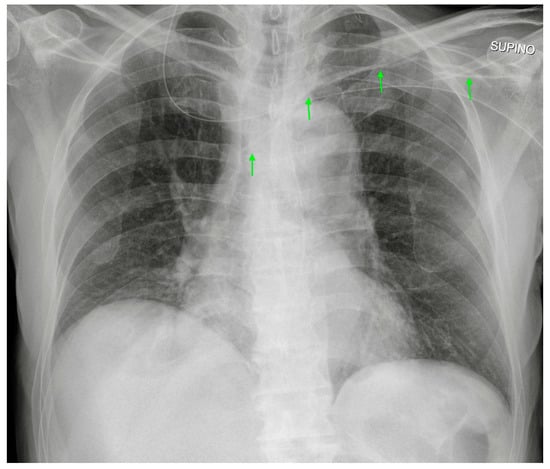

3.2. Peripherally Inserted Central Catheter (PICC)